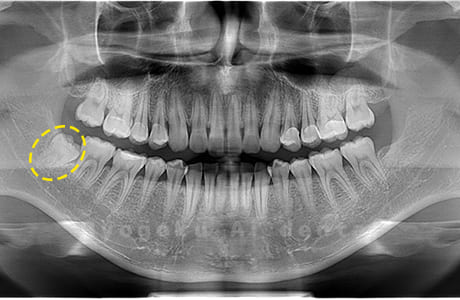

Case04

-

- 原因

- 上顎の親知らず、下顎の水平埋伏の親知らず

- 治療内容

- 上顎の親知らず、下顎の水平埋伏の親知らずを抜歯したケースです。

<リスク・副作用>

手術後は痛み、腫れ、痺れなどの副作用が生じる場合があります。